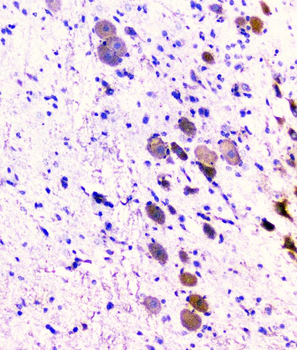

100 μg - PGP9.5 antibody [orb6713]Featured

ELISA, ICC, IF, IHC-P, WB

Human, Mouse, Rat

Rabbit

Polyclonal

Unconjugated

100 μg - FOXP3 antibody [orb34127]Featured